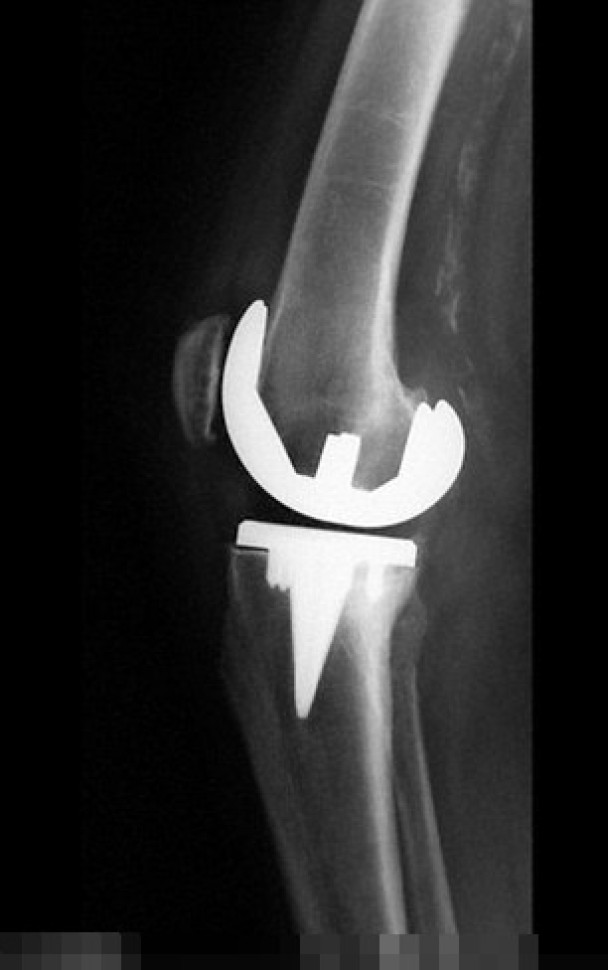

美国一名妇人因用牙线不当,令其假膝盖骨关节受口腔细菌感染。

医生指妇人口腔的细菌随血液流到其假膝盖骨,导致关节受感染。

(蜘蛛网报道)美国一名65岁妇人5年前因为骨关节炎把膝盖骨换掉,半年前她的右腿和膝盖骨开始疼痛,医生建议她接受针灸纾缓痛楚。惟妇人的膝痛愈来愈严重,膝盖更肿起来,身体又发冷。她立即前往急症室,医生抽取其膝盖关节内的液体化验,结果发现其膝盖骨受一种名为“戈登氏链球菌”(Streptococcus gordonii)的口腔细菌感染,而原因竟然与她使用牙线有关。

有关病例刊登于《英国医学期刊病例报告》(BMJ Case Reports),负责撰写报告的医生指,该名妇人因为用牙线不当令牙肉流血,以致其口腔内滋生“戈登氏链球菌”,细菌之后随血液流到其膝盖,令其假膝盖骨关节亦受感染。医生其后动手术,为妇人清洗膝盖骨上的细菌,并处方抗生素治理,妇人现时正康复。医生又指这是北美首个病例,在此之前医学文献只有1宗同类个案记载。